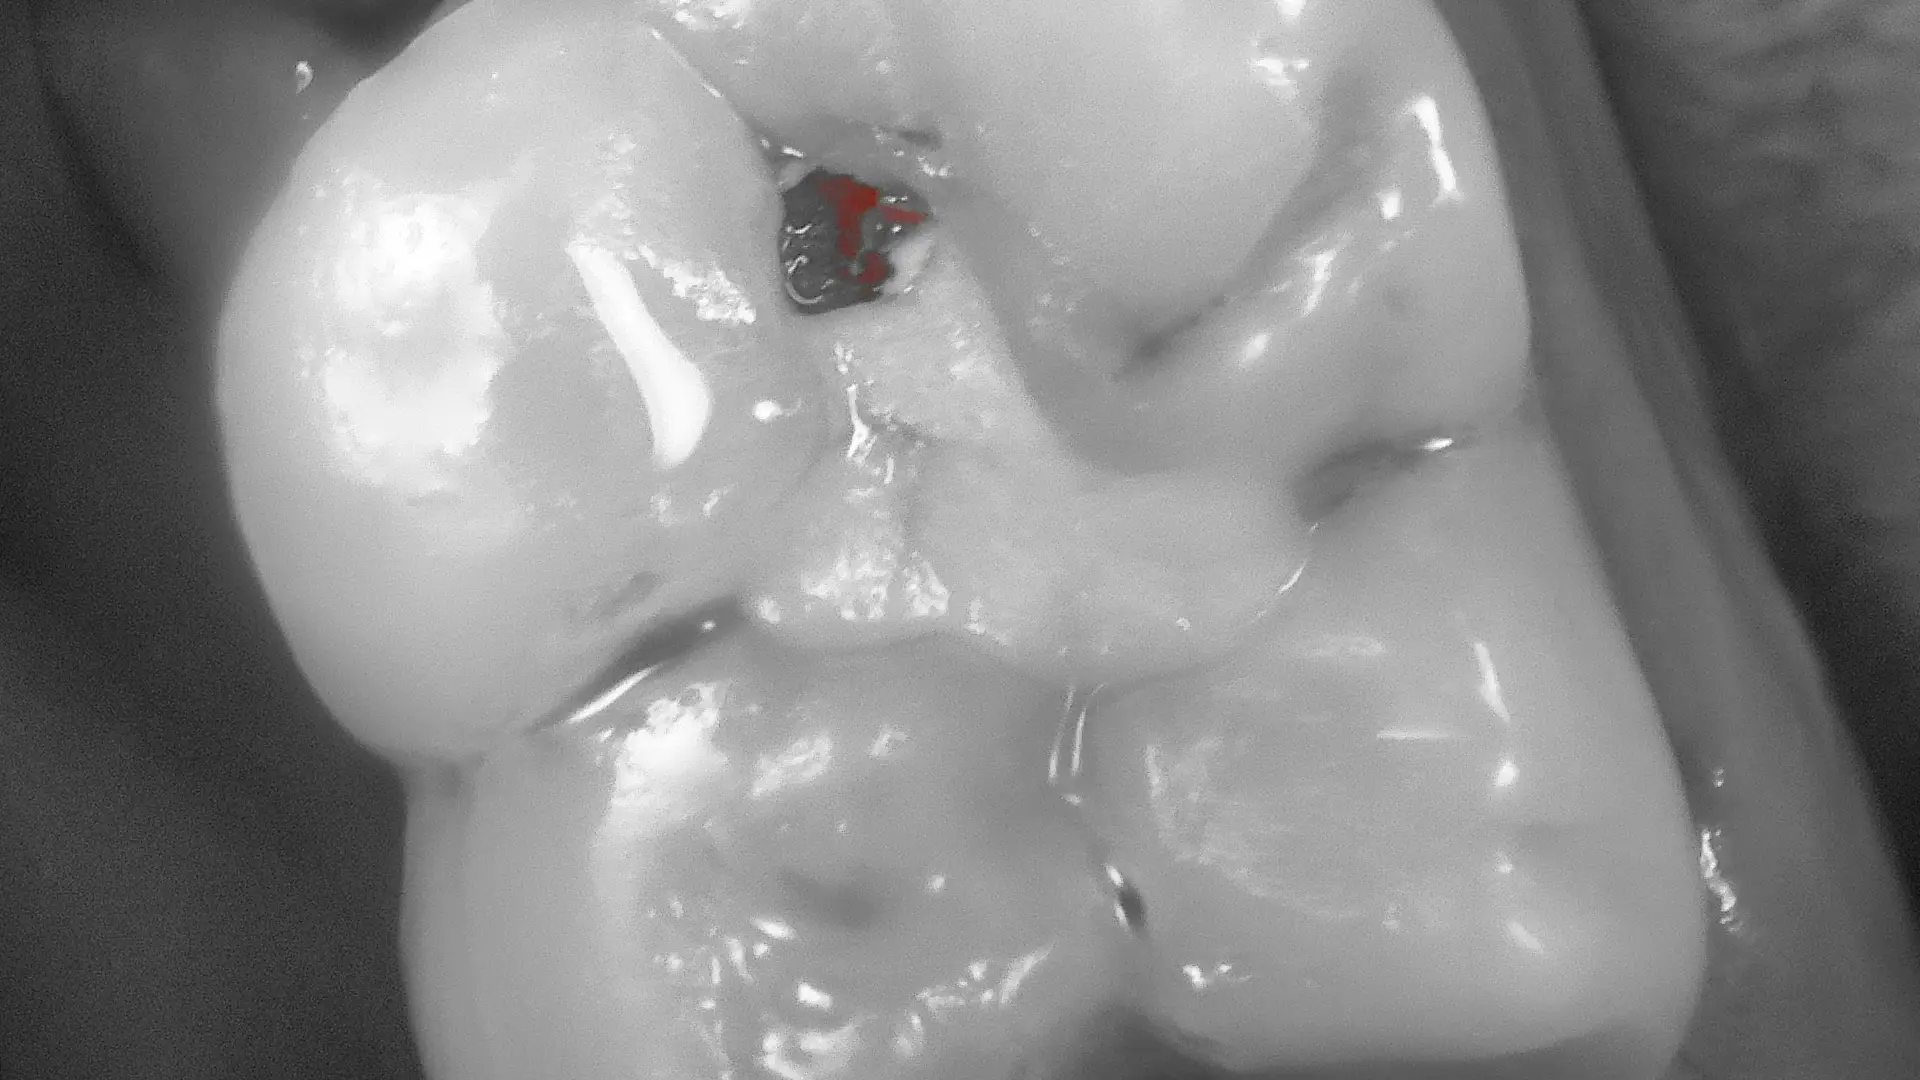

Early Caries & Plaque Detection

Patented Acteon fluorescence highlights early carious lesions and plaque as distinct colour changes — visible before they appear on X-ray or to the naked eye.

Experience the exceptional Full HD detail and fluorescence diagnostics in real patient cases — from early caries detection to minimally invasive restorations.